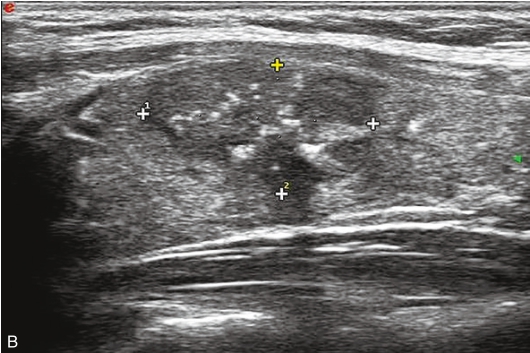

甲状腺右叶中上部见一低回声结节,大小约0.7cm×0.7cm×0.8cm,边界清楚,形态尚规则,内可见少许点状强回声。CDFI示结节内及周边可见较丰富血流信号,见图1-9-5。

图1-9-5 甲状腺髓样癌常规超声声像图

A.甲状腺右叶结节横切面;B.甲状腺右叶结节纵切面;C.甲状腺右叶结节CDFI血流图

甲状腺右叶上部结节超声造影后早于周围组织开始出现增强,达峰时呈偏低增强表现,边界不清,范围未见明显扩大,之后快速消退,晚期呈明显低增强,结节旁甲状腺被膜增强完整,见图1-9-6、ER1-9-3。

造影后结节内呈不均匀偏低增强表现,增强边界不清,增强晚期快速消退。